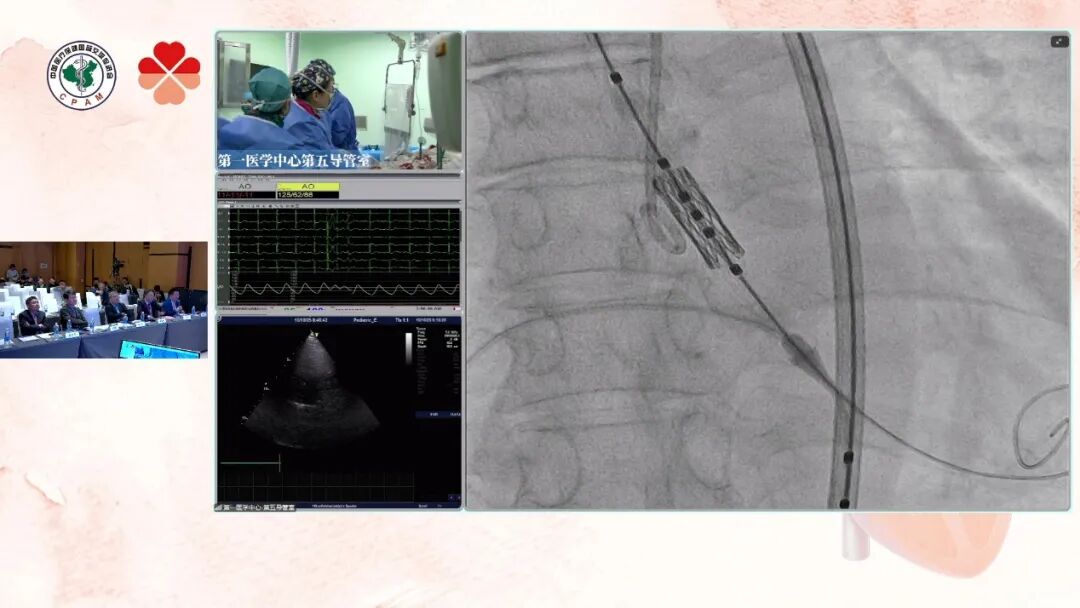

患者为61岁女性,主诉活动后胸闷1年,近期症状加重。既往病史包括冠心病6年、甲亢26年、高血压2年及家族性高胆固醇血症。术前超声提示主动脉瓣重度狭窄伴中度关闭不全,同时存在先天性房间隔缺损(筛孔型)及二尖瓣轻度关闭不全。术前CT分析显示患者瓣环较小,瓣叶中度钙化且分布均匀,双冠开口高度临界,存在一定冠脉阻塞风险,为手术操作增加了挑战。术中以右股为主入路,植入20# 瓣膜,减容1mL,球囊匀速、缓慢充盈并足量保压5秒后释放瓣膜。随后行球囊后扩,瓣膜充分展开、位置精准。术后造影显示瓣膜位置良好、形态正常,手术顺利完成。

瓣膜输送到位